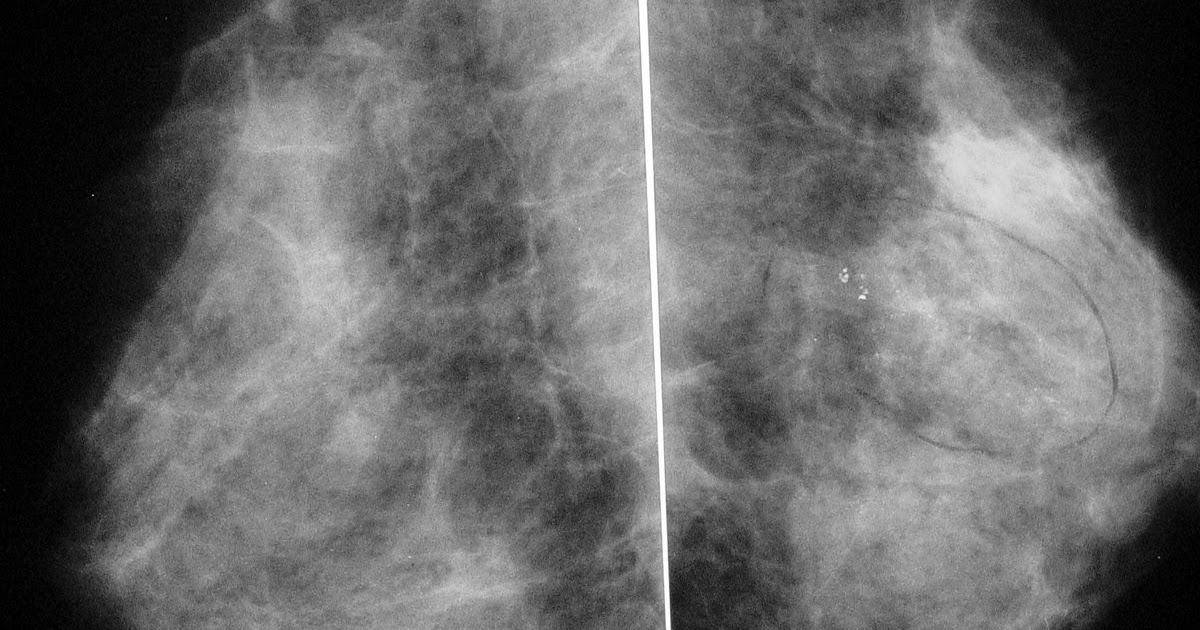

Mulheres com mamas densas têm maior risco de desenvolver câncer de mama

Clínica Afrânio Coelho de Oliveira CÂNCER INICIAL DA MAMA MAMOGRAFIA